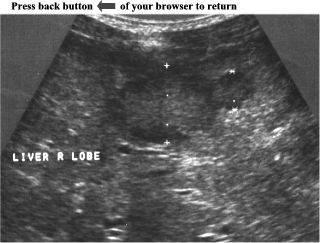

CASE

6:

Ultrasound

examination

of

the

right

liver

lobe

revealed

two

adjacent,

hypoechoic,

well

defined

masses.

size

masses

were

2,6cm

and

1,3cm

respectively.

Both

had

hypoechoic

halo

around

which

made

easily

distinguishable

from

surrounding

parenchyma.

rest

parenchyma

was

normal.

ANSWER:

Hepatic

Metastases